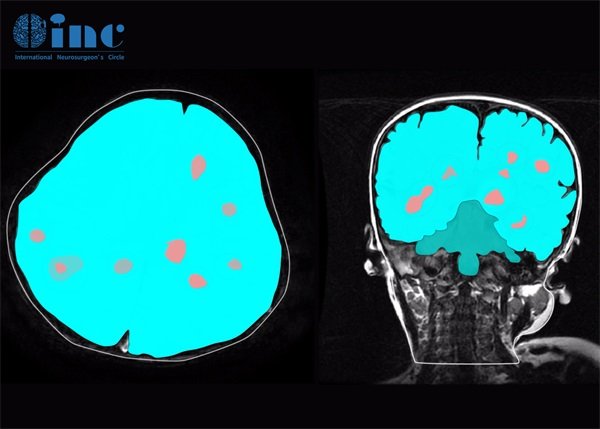

CT检查在判断颅内病变方面,具有较好的敏感性和特异性,但其对不同性质病变的识别能力有所不同。对于颅内海绵状血管瘤,CT能够通过其特征性的影像学表现进行初步判断。

CT影像上,海绵状血管瘤通常呈现为低密度的病变,可能伴有边缘清晰的特征。这些肿瘤与周围脑组织的分界较为明显,因此在CT图像中,海绵状血管瘤相对容易被识别。

然而,CT的效果受到许多因素的影响,包括肿瘤的大小、位置以及周围组织的状态。在某些情况下,海绵状血管瘤可能被其他病变所掩盖,导致误诊或漏诊。因此,尽管CT是一种重要的检查工具,但在确诊方面,结合其他影像学检查,如MRI,可能会提供更为全面的信息。

颅内海绵状血管瘤的诊断一般依赖于影像学检查,常用的手段包括CT和MRI。CT虽能提供快速的肿瘤评估,但MRI具有更高的分辨率,对软组织病变的识别效果更佳。

颅内海绵状血管瘤在影像学上通常表现为低密度或边缘清晰的病变。使用CT扫描时,病变可能显得比周围组织更暗,显示出与脑组织良好的界面。MRI则能够提供更详细的血管成分和周围组织的状态。